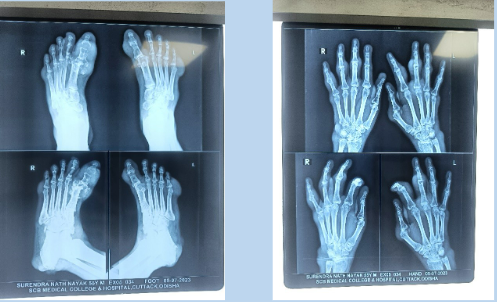

(Image 1) Multiple tophi on bilateral foot

(Image 3) Tophi over the bilateral foot

(Image 4) Multiple tophi over bilateral hand

(Image 6) X-ray showing martels sign and erosions of bone and joint

A 40-year-old male presented with nodular growths on b/l feet with generalised pain at b/l knee joint, ankle, and MTP joint. The patient was a known alcoholic. O/E-multiple hard nodular swelling over b/l feet largest being on the right 1st MTP joint of size 5*4 cm, and all nodules with chalky white tip and some with whitish discharge.

Laboratory findings and radiologic examination

Lab reports revealed se uric acid 13.2 mg/dl, ESR-50mm/1st hour, CRP-26mg/L, radiologic examination showed soft tissue swelling & destruction of 1st MTP joint.

A 60-year-old man with a known case of chronic medical renal disease & vitiligo presented with b/l lower limb swelling and decreased urination and incapacitating pain with nodular swelling over b/l upper limb and lower limbs O/E- multiple hard nodular swelling over foot and hand near the joints with whitish discharge from some nodules.

Laboratory findings

On work up blood reports showed serum uric acid of 19.2 mg/dl and urea, creatinine -102mg/dl, 6.7 mg/dl respectively. ESR- 60/1st hour, CRP-40.

Radiologic examination

An x-ray of the foot showed joint erosion with martle sign.